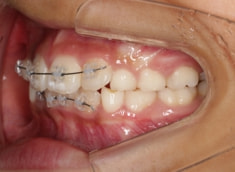

治療中